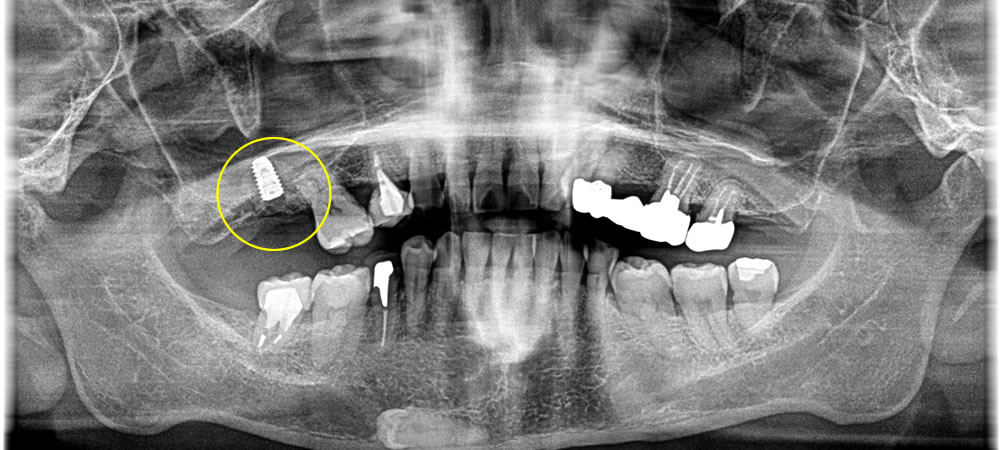

豊富な経験を持つ院長が、インプラント治療を担当します。CTによる精密な検査・診断に基づき、安全性を第一に考えた治療計画を立てます。骨の量が少ないなどの理由で他院にて治療が難しいと判断された場合でも、骨を増やす処置などを用いて対応できる可能性があります。まずは無料相談にお越しください。

インプラント手術を実施する際は、事前にCTによる精密検査を行います。